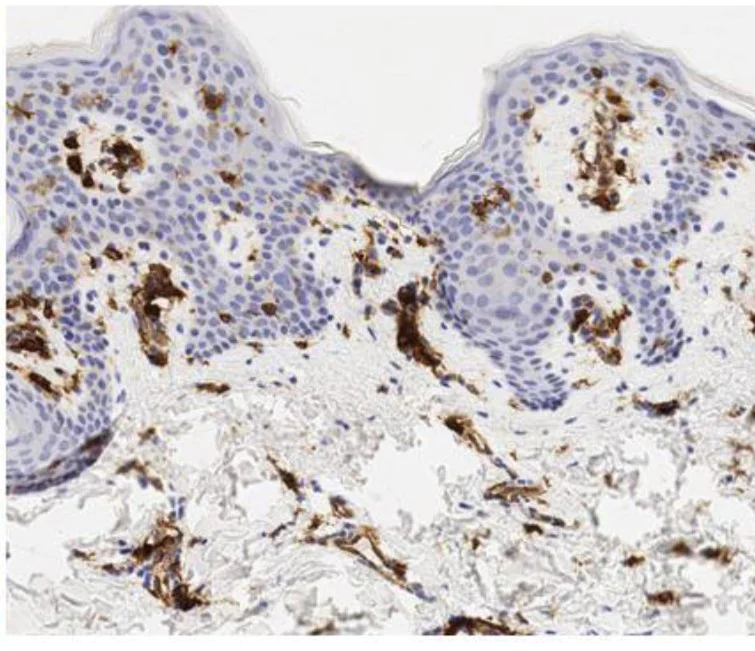

Immunohistochemistry (Formalin/PFA-fixed paraffin-embedded sections) - Anti-HLA-DR antibody [TAL 1B5] - BSA and Azide free (AB176408)

Immunohistochemical analysis of paraffin-embedded human skin tissue labeling HLA-DR with ab20181 at 0.1 μg/ml followed by Leica DS9800 (Bond™ Polymer Refine Detection). The section was pre-treated using heat mediated antigen retrieval with sodium citrate buffer (pH6, epitope retrieval solution 1) for 20mins. The section was then incubated with ab20181, 0.1ug/ml, for 15 mins at room temperature and was then detected using an HRP conjugated compact polymer system. DAB was used as the chromogen. The section was then counterstained with haematoxylin and mounted with DPX.